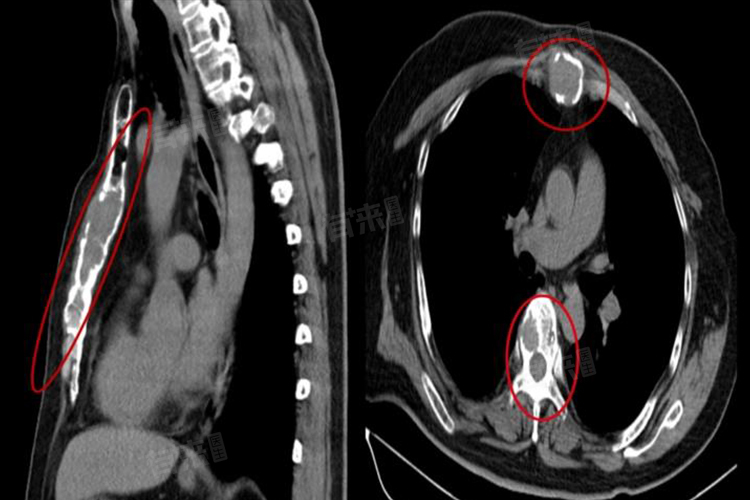

5、淋巴结肿大:多发性骨髓瘤晚期时,会发生广泛的转移,其中就包括淋巴结转移,就会出现淋巴结肿大的现象,肿大的淋巴结通常质地坚硬,移动度差,大小不等,还可能伴有局部皮肤红肿、热痛等症状。